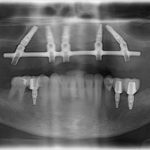

All on 4 Case 1

After after all on 4 x-ray view female patient case 1

after all on 4 x-ray view female patient case 1

Male

Dr. Cavaretta